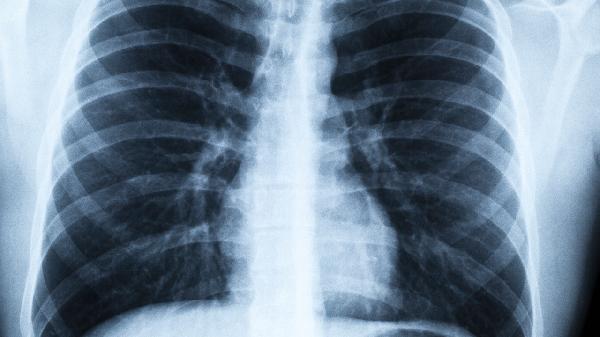

二、肺癌筛查的黄金标准

1、低剂量螺旋CT

相比X光片,它能发现小至2mm的肺结节,检出率提高20倍以上。建议40岁以上吸烟者每年检查一次。

3、"体检胸片正常就安全"

普通胸片会漏诊80%的早期肺癌,这就是为什么很多患者确诊时已是晚期的原因。